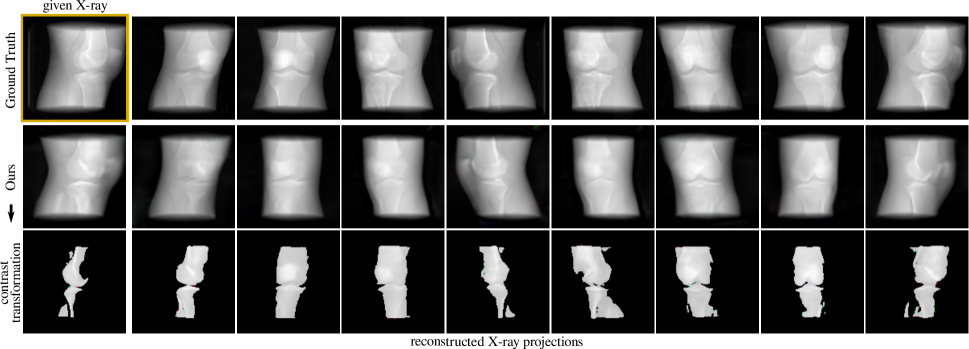

Figure 3: Knee renderings from continuous viewpoint rotations showing tissue and bone. Given a single-view X-ray from a CT, we can generate the complete set of CT-projections within a full vertical rotation by slightly fine-tuning a pretrained model along with the shape and appearance latent codes.

We evaluate our model’s representation for 3D-aware DRR synthesis given a single-view X-ray as input. We find that despite the implicit linear network’s limited capacity, our model can disentangle 3D anatomy identity and attenuation response of different medical instances, which are retrieved through the described reconstruction reformulation in II-C3. Our model can also facilitate distinguishing bone from tissue via a contrast transformation, as it renders a brighter pixel value for denser structures (e.g. bone) (Fig. 3).

Table I summarises our results based on the peak signal-to-noise ratio (PSNR) and structural similarity (SSIM), which measure the quality of reconstructed signals and human subjective similarity, respectively. We find that our generative loss can achieve a reasonable perception-distortion curve in renderings and show consistency with the location and volumetric depth of anatomical structures at continuous viewpoints compared to the ground truth.